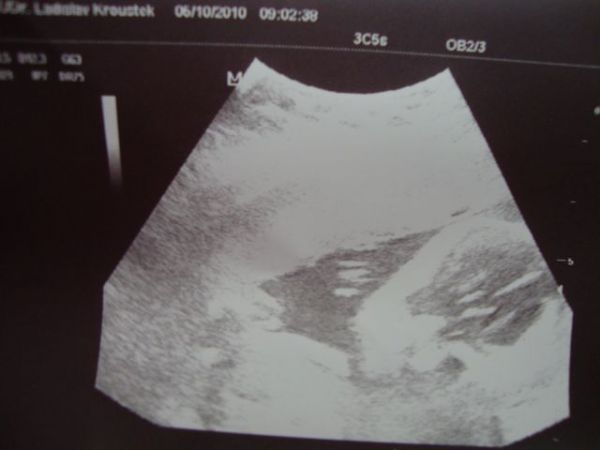

mysicka-mys 05.10.2010 Detail Ahojky holky, tak jsem dneska byla v poradne... Komentáře jsou momentálně nedostupné. Děkujeme za pochopení.